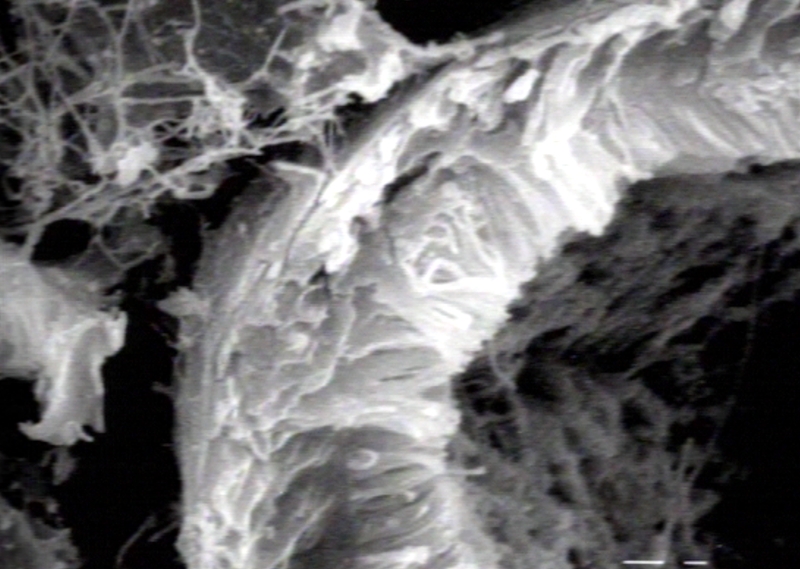

ELECTRON MICROSCOPY: URINARY: KIDNEY: PROXIMAL CONVOLUTED TUBULE, unlabeled; Scanning Electron Micrograph, PROXIMAL CONVOLUTED TUBULE